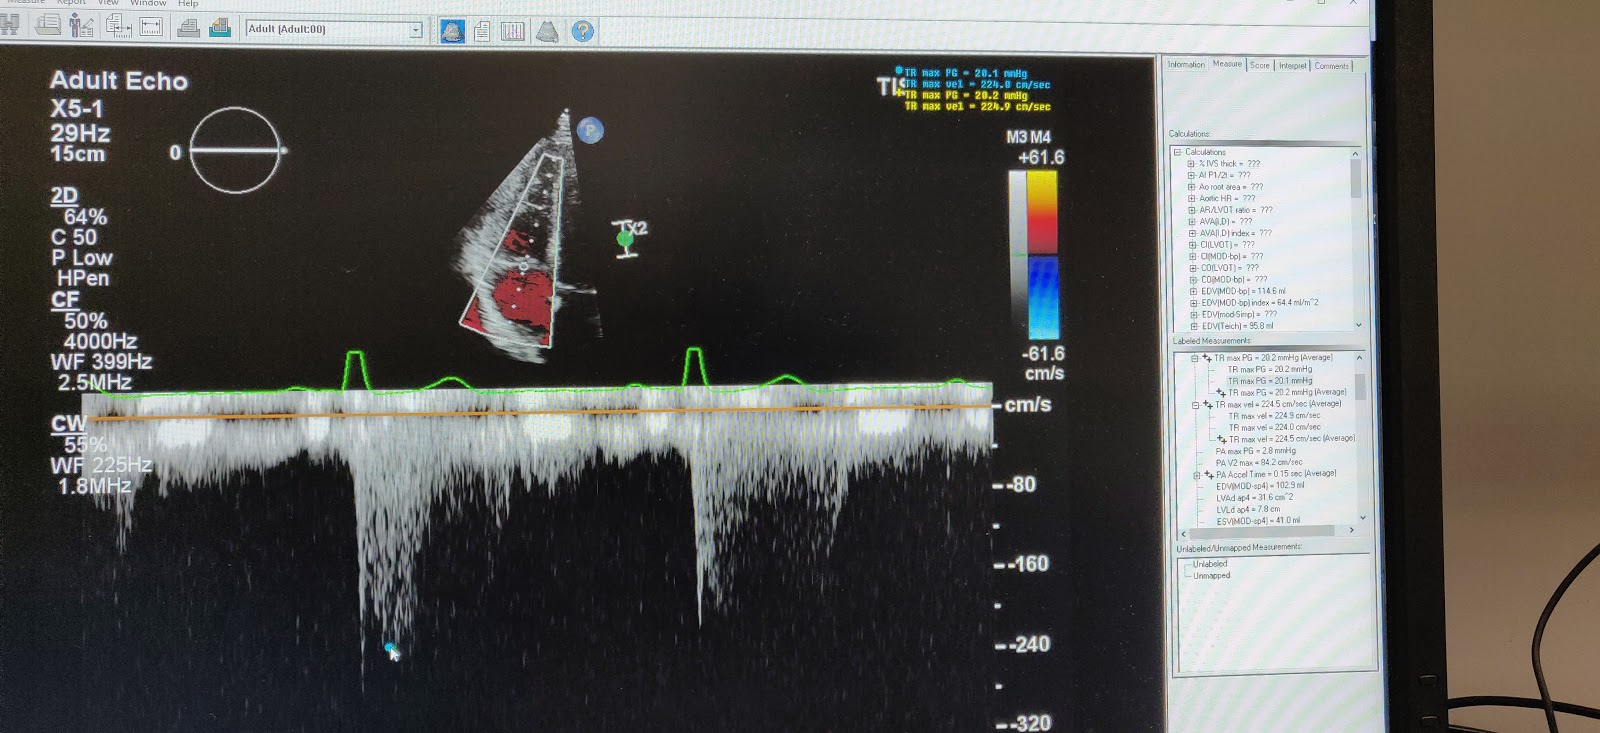

![]() |

| Echocardiography analysis |